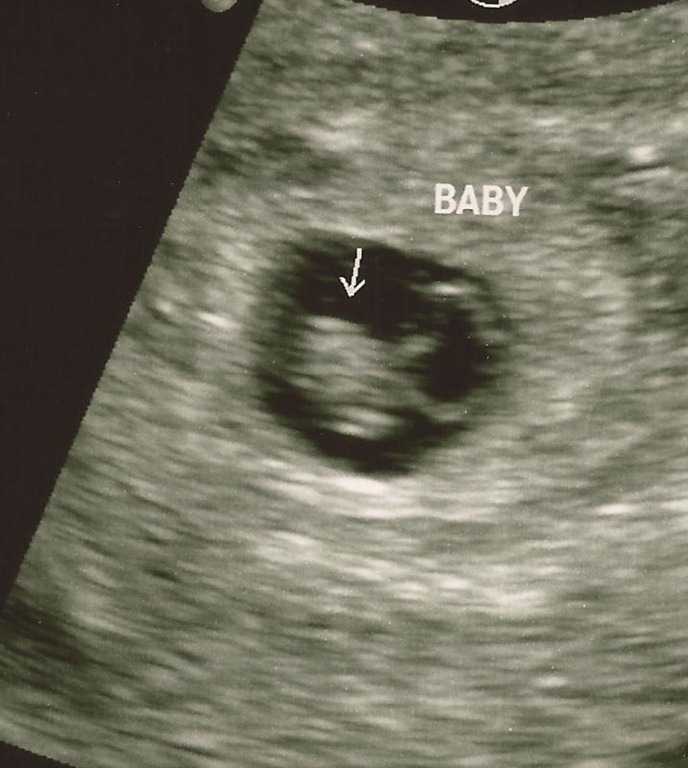

I went for my first pre-natal appointment on August 3 and saw the heartbeat and got a picture of the little bean.

angel 2_8.5.11_6wks3days

When I got there she had me hop on the table and she broke out the Doppler machine which can detect the sound of the heartbeat at 10 weeks, which is where I’m at. She moved it around and worked it for a good 3 minutes without finding a heartbeat. It was that dreaded moment that every mother fears – going in for a regular exam and hearing nothing on the machine. She said that sometimes you can’t hear it yet and we’d do an ultrasound. After a minute of not seeing anything on that she moved to the vaginal ultrasound. I already knew at this point. My heart knew. My mind knew. Even though the doctor hadn’t said the words, I knew.

After taking some measurements she turned the monitor around and showed me that there was no visible heartbeat. According to her measurements, it looked like the baby had stopped growing at 7 weeks 4 days, which was 3 weeks ago. But she wanted to be sure. So she sent me upstairs to radiology, where they have better equipment. She cautioned me not to expect a miracle but we needed to make extra sure the baby wasn’t viable before proceeding with anything else.

As the tech did her thing, checking all the areas and taking measurements, I just watched the monitor. I saw the little bean that was my child, laying in its little sac. It looked peaceful and still. Very still. No heartbeat. No movement of any kind. Just a shape.